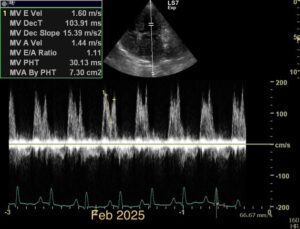

Chronic stage C MVD.TID Pimo and Lasix(high dose), ACEi and Spirono. Doing well. Recheck: Idexx GHP= CBC-NSF ,SDMA 15,BUN 14.1mmol/L, Creat 79umol/L. US: Cornell Indx LVd=1.46(prev2.1), LV septal flattening with diastolic dip,LAAO=2.47,Evel1.45m/s, TVregPG-68mmHg,HV distension-mod ascites.LV and LA underloading via diuretics and PHT (mild PHT past).PHT more pre vs post cap based on small LVsize? Consider Sildenafil/L Arg.Concerned about developing L CHF.Is CHF less likely adding PDE5i with MVD/PHT in underloaded LV than same scenario with vol overloaded LV at similar staging. MVPG=120.3mmHg

Dan, considering the LAE in addition to LV underloading – does this dog have mitral stenosis?? As you suggested, with this degree of LAE I would expect LVE as well….

Thanks. Not sure if any sig. MV stenosis?? My experience limited.3 PWD from diff times. Ls7 vid. is from 2024,initially thinking reverse remodelling where the lasix lowering preload and Pimo is decreasing LV size via decreased resist/increase cxn while LA no change because it’s a chronic filled remodeled saggy bag receiving Regurge volume??